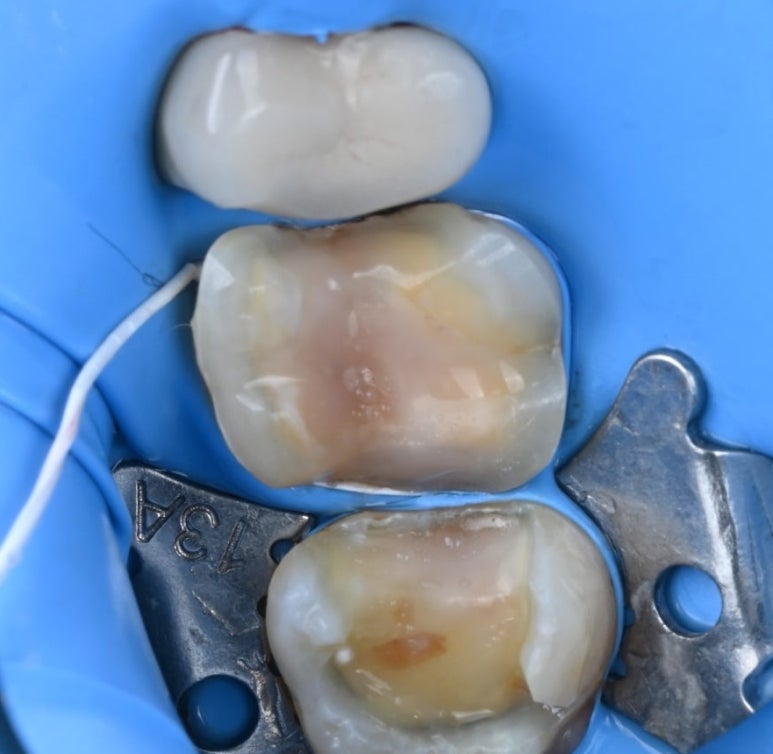

25.11.11 금인레이 제거 후 모습

앞쪽 어금니는 인레이를 제거해 보니

충치 범위가 넓어, 치아의 씹는 면을

전체적으로 보호해 주는

'세라믹 오버레이(Overlay)'를 적용하기로

결정했습니다.

25.11.11 앞쪽 어금니(#16) 금 인레이 하방에서 발견된 충치